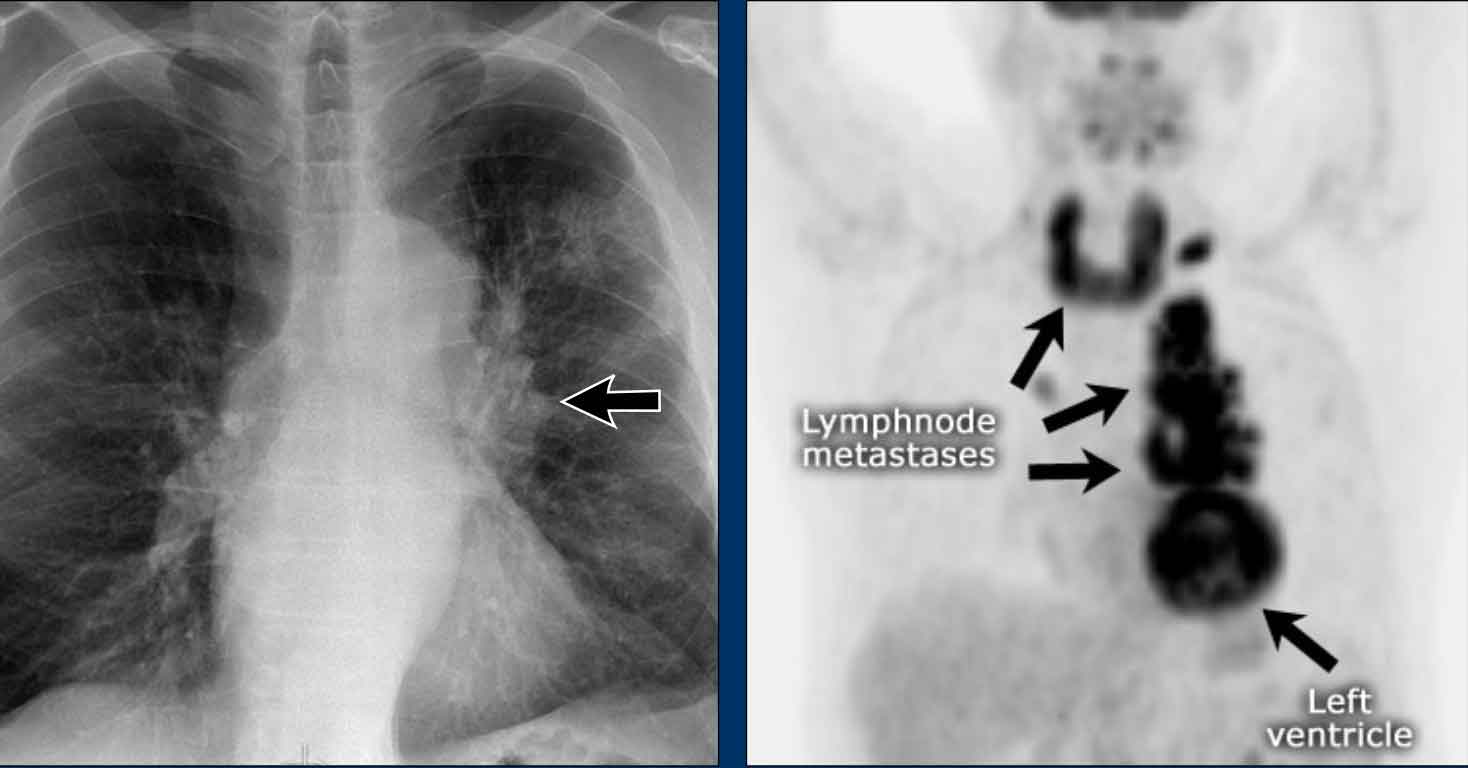

Hidden area (5): Mass Behind the First Rib

In some patients, an accessory joint at the anterior aspect of the first rib may simulate a mass, as we learned earlier.

However this area is also a "hidden zone", where true lesions can be masked.

• In this case, a small lung carcinoma was obscured by the left first rib on the PA view.

• On the lateral film, the lesion is visible in the retrosternal space.

Continue with the PET-CT...

Subsequent PET-CT imaging confirmed a hypermetabolic tumor (arrow), with metastases to the bone and liver.

• Diagnosis was confirmed via biopsy of an osteolytic metastasis in the iliac bone.